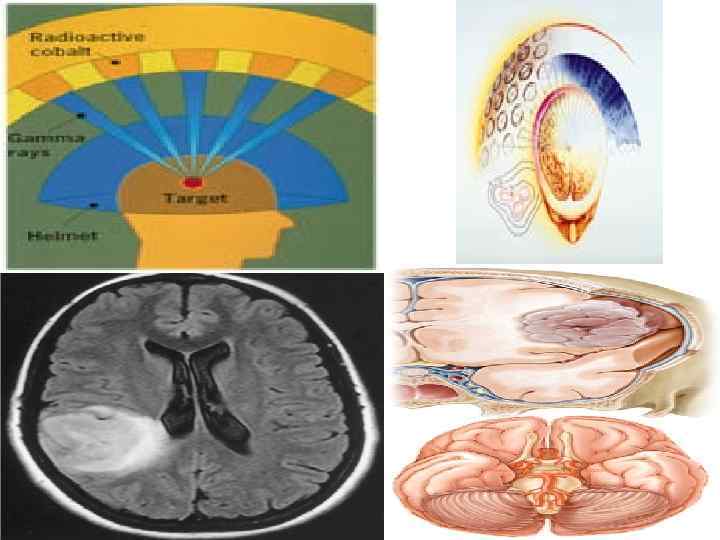

Существует несколько типов аппаратов для стереотаксической радиохирургии: Gamma Knife, LINAC, XKnife, Synergy. S, Trilogy, Cyber. Knife, Novalis и Сyclotron. Принцип работы у всех аппаратов одинаков, а различаются они источниками энергии и методами наведения излучения на цель. Так например LINAC это линеарный акселератор, который использует в своей основе рентгеновские лучи и электромагнитные волны позволяющие достичь энегии в 46 Me. V. Во время процедуры лечения аппарат вращается вокруг пациента, обеспечивая точное излучение, фокусирующееся на опухоли. В аппарате Gamma Knife используется 201 источник радиоактивного кобальта и электромагнитные волны, с возможностью достичь максимальной энергии до 1, 25 Me. V 76

Примеры радиохирургии Метастаз лобной доли Восемь месяцев после лечения Результаты лечения артериовенозной мальформации через 2 года после лечения, проведенном на аппарате «Leksell Gamma. Knife»